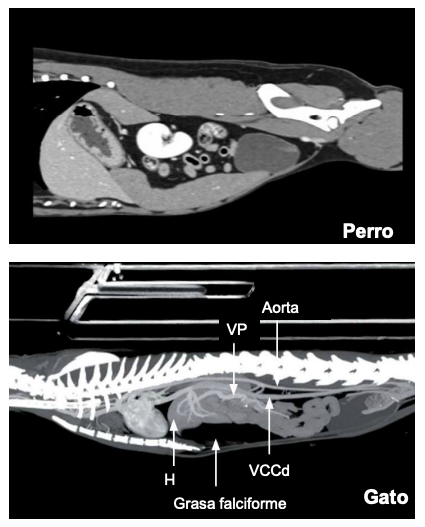

En perro mas achatada, gato mas alargado. musculo del psoas en gato obscura parte del diafrgama.

Topogradía abdominal del perro: Tac o TC del tejid blando, vista dorsal

Generalmente las imagenes de tac están espejadas

En gato el bazo siempre esta en la izquierda, el perros la cola puede estar a la derecha